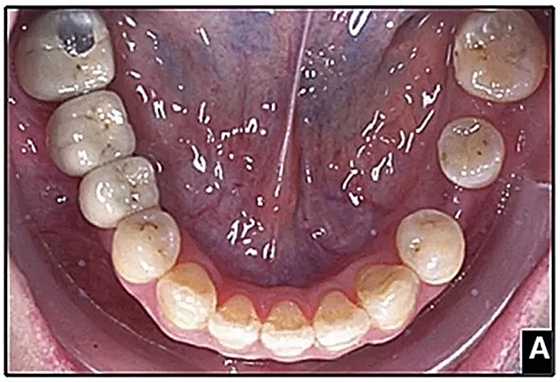

經(jīng)過32個月的活動治療后,上下牙弓排齊良好,下頜第一磨牙區(qū)的雙側牙間隙可用于種植(圖12,A和13,A)。

圖15.A,去除固定裝置一個月后,下頜左側第二前磨牙復發(fā),移動到種植體愈合的部位; B,B-0表示開始再治療,通過鏈圈和推簧的矯正復發(fā); C,B-9是治療結束后3個月回訪時下頜弓的咬合面觀,這是再治療階段的9個月。下頜左側第二前磨牙和第三磨牙的頰面粘合一個固定保持器,以防止復發(fā)。